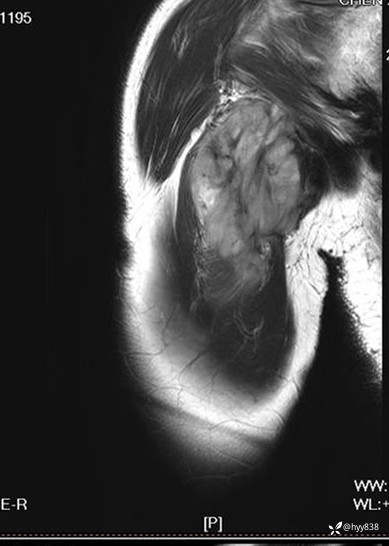

CE